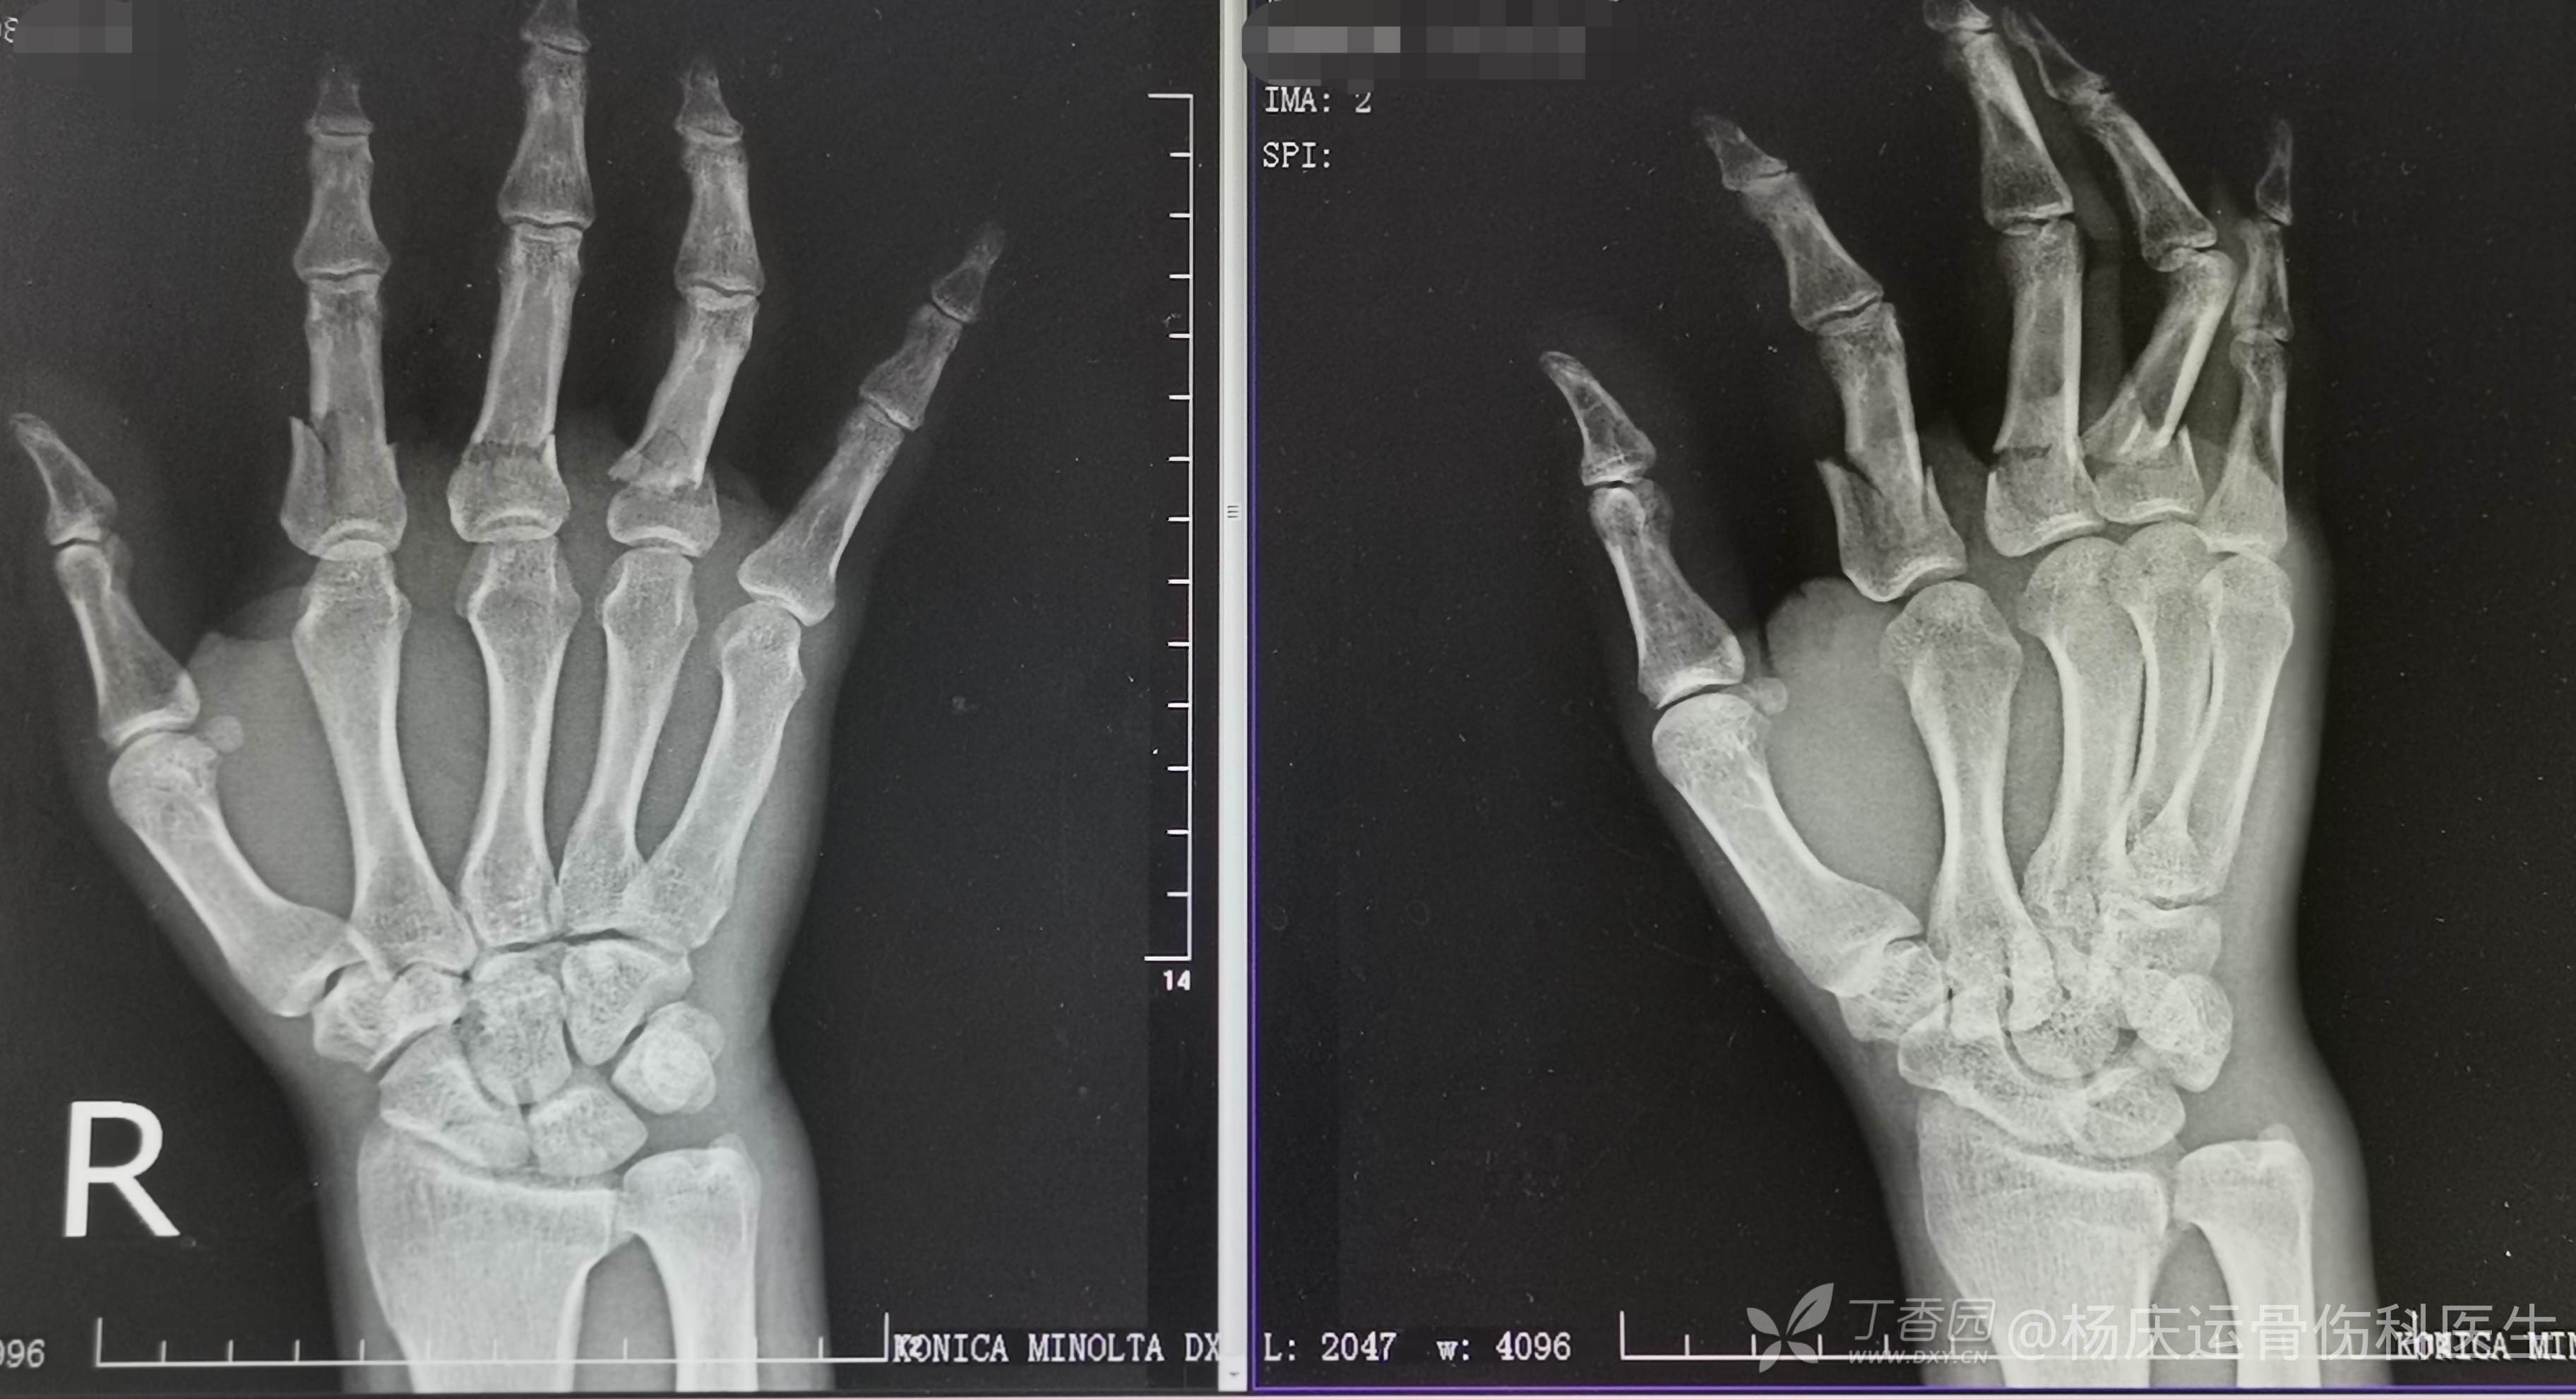

首诊片